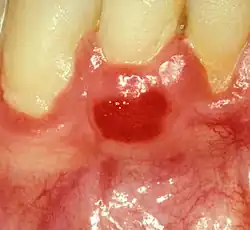

Plasma cell gingivitis in an adult (histologically verified). |

Plasma cell gingivitis appears as mild gingival enlargement and may extend from the free marginal gingiva on to the attached gingiva.[6] Sometimes it is blended with a marginal, plaque induced gingivitis, or it does not involve the free marginal gingiva. It may also be found as a solitude red area within the attached gingiva (pictures). In some cases the healing of a plaque-induced gingivitis or a periodontitis resolves a plasma cell gingivitis situated a few mm from the earlier plaque-infected marginal gingiva. In case of one or few solitary areas of plasma cell gingivitis, no symptoms are reported from the patient. Most often solitary entities are therefore found by the dentist.[2]

The gums are red, friable, or sometimes granular, and sometimes bleed easily if traumatised.[6] The normal stippling is lost.[7] There is not usually any loss of periodontal attachment.[6] In a few cases a sore mouth can develop, and if so pain is sometimes made worse by toothpastes, or hot or spicy food.[7] The lesions can extend to involve the palate.[7]